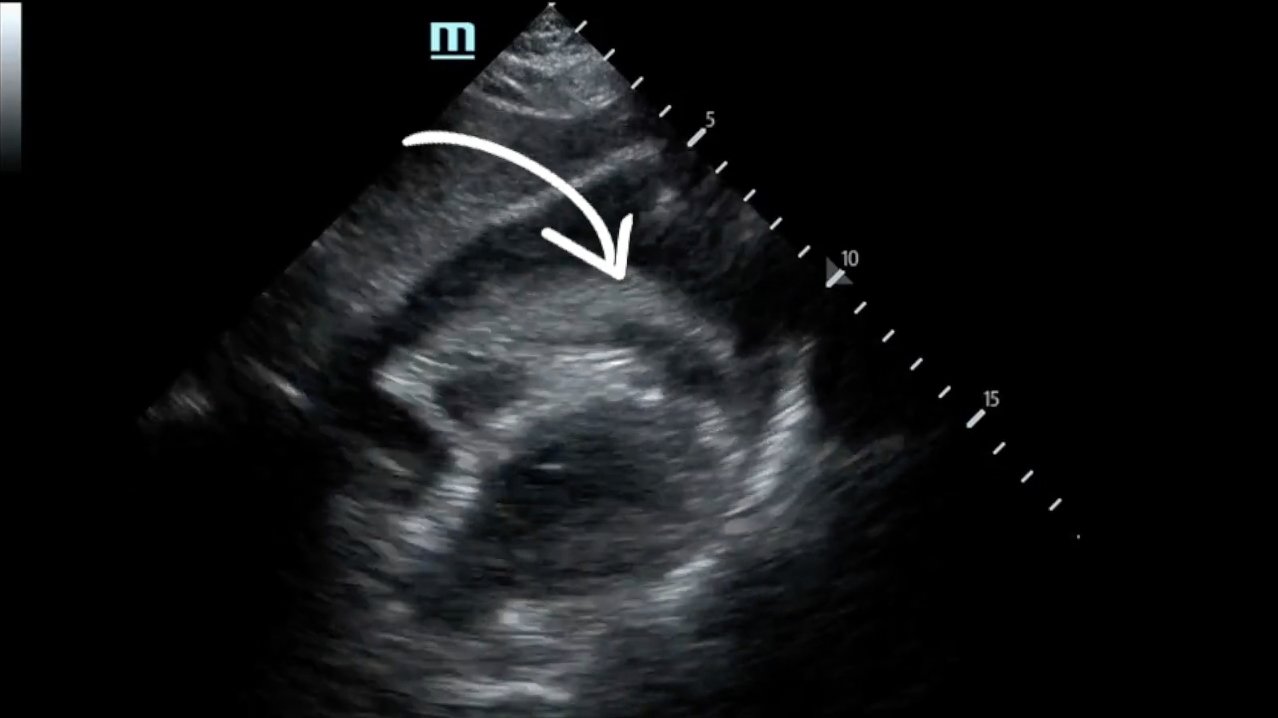

Focused assessment with sonography in trauma (FAST) scan was positive for a clinically significant pericardial effusion as evidenced by the hypoechoic fluid around the myocardium, indicated by the blue arrow in image 2. Findings are also consistent with tamponade process as evidenced by restricted expansion and collapse of the right ventricle during diastole. The hyperechoic floating structure between the pericardium and myocardium, adjacent to the right ventricle, represents a pericardial clot, indicated by the white arrow.The density of the pericardial clot differs from that of the myocardium, thus serving as an additional variable to avoid confusing this as part of the myocardial structure.